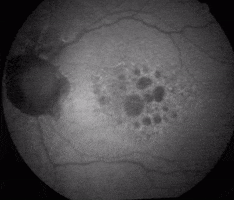

Atrophic Amd Progression GIF